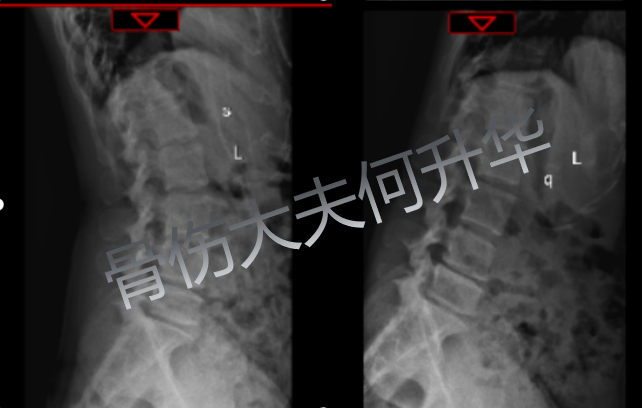

入院时 X 线动态体位提示

腰椎 4/5、腰椎 5/骶骨 1、椎间不稳定